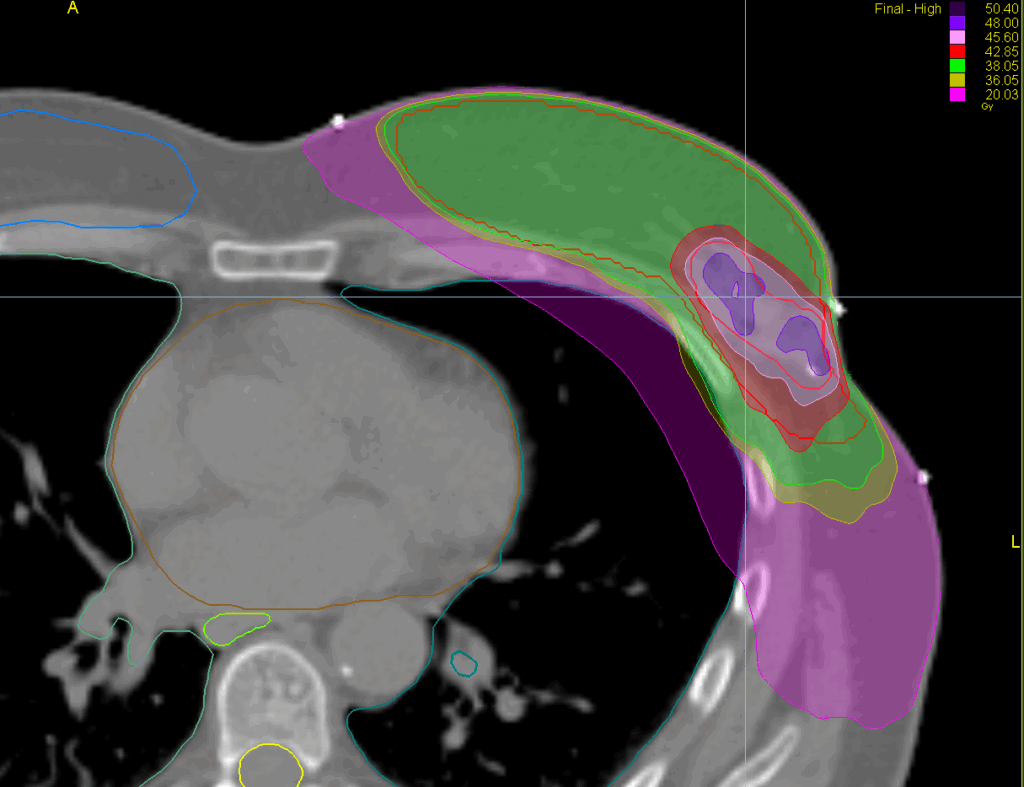

Treatment Plan Images

Fractionation / Protocol Used

40/48 Gy in 15 fractions

PTV(s) Volume, Length

660 cc, 25 cm

Mode

TomoHelical™ 5cm